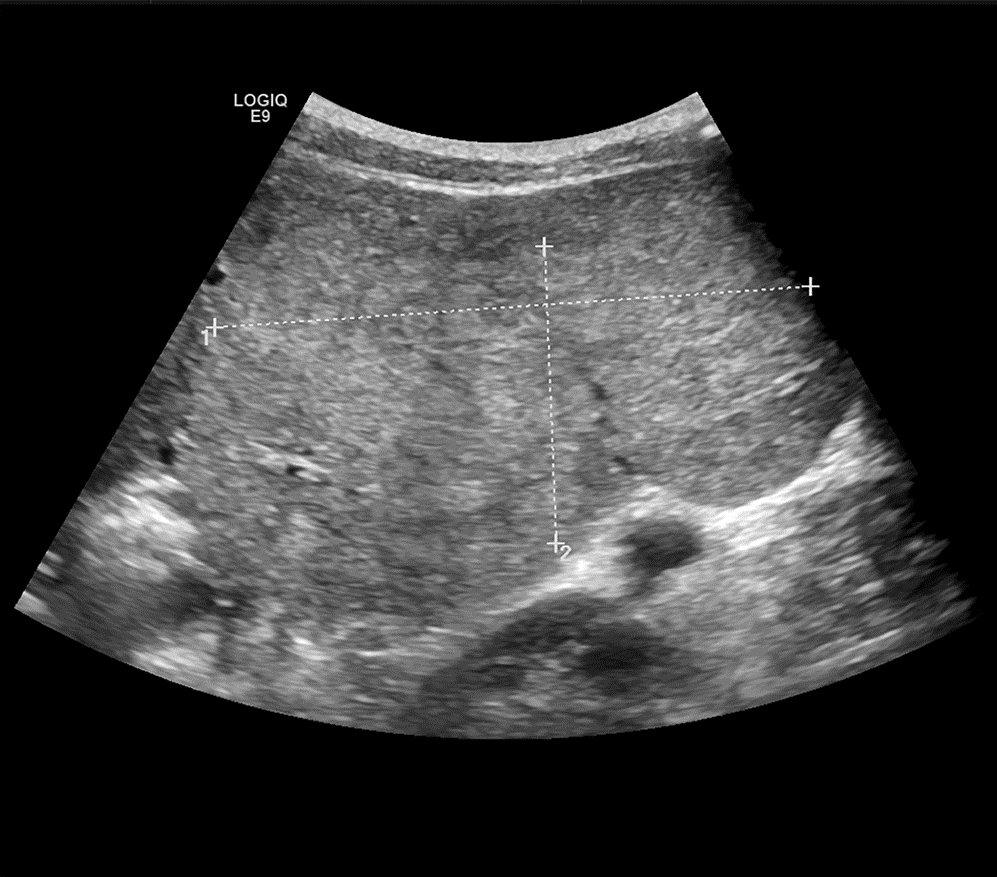

Giant focal nodular hyperplasia of the liver in children: A case report

Cheng CHEN, Junjie WANG, Yakun WU

2022, 38(6): 1370-1372. DOI: 10.3969/j.issn.1001-5256.2022.06.029

Abstract(1058) HTML (390) PDF (3134KB)(66)

Abstract: